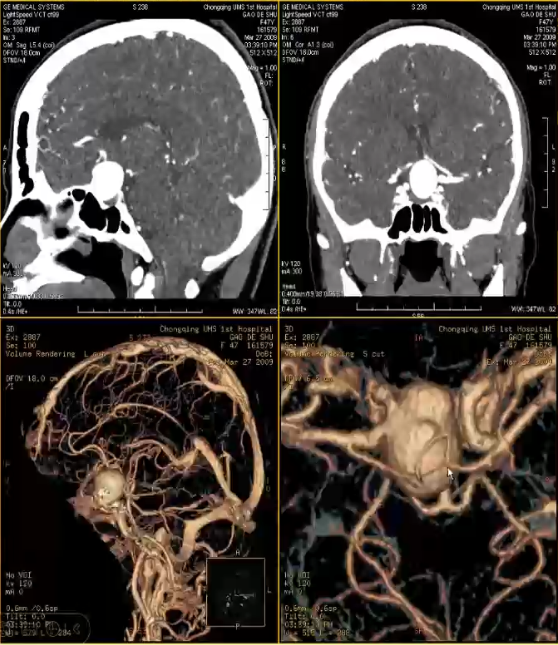

女,47岁,视力下降3月,CT平扫鞍区及鞍上高密度肿块,考虑垂体瘤,不除外动脉瘤,MRI垂体显示正常病变呈流空信号,增强后中心片状强化,病变的相位方向明显搏动伪影,VCTDSA清晰显示左侧颈内动脉床突上段动脉瘤